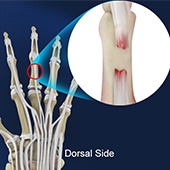

Extensor Tendon Injuries

Tendons are bands of tissue connecting muscles to bones. The extensor tendon is a strong, smooth cord that connects finger bones to muscles in the hand. Extensor tendons are located just under the skin, directly on the bone, on the back of the hand and fingers. They allow you to open your hands and move or straighten your wrist, fingers, and thumb.